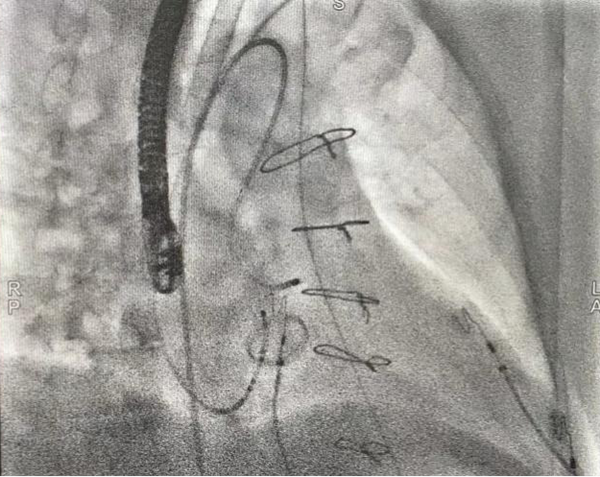

三维显示主动脉瓣下消融靶点

主动脉瓣上激动标测